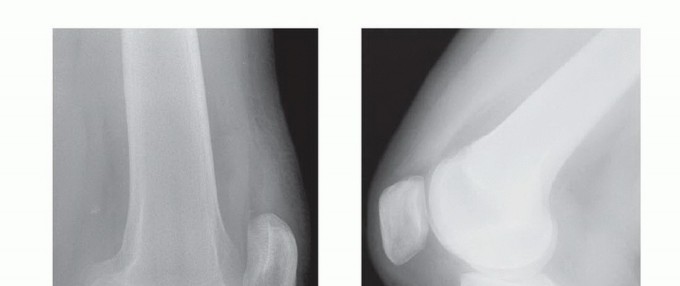

DEFINITION Patellar instability in children and adolescents usually involves an episode of complete dislocati…